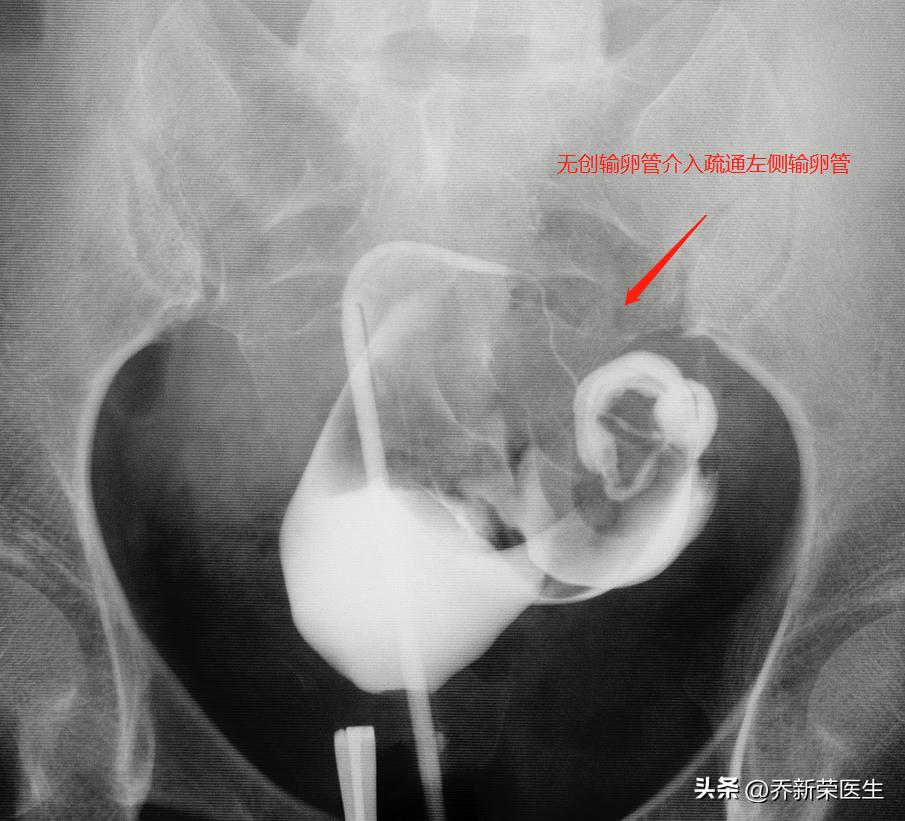

目前的治疗方式里,建议还是以保守的无创伤治疗:一 是比较慢的方法,中医中药,一般最低疗程三个月,三个月后复查造影评估是否有改善,治疗过程中要避孕,避免宫外孕的发生,年轻人不急可以试试。二 是快速直接的方法,输卵管介入治疗,情况好的下个月开始备孕。